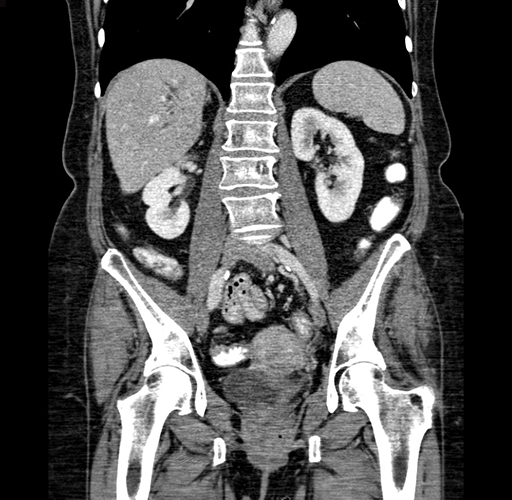

Pre-Chemo: Coronal Venous

Coronal Venous